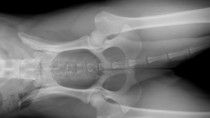

Legg-Calve-Perthes Disease in Dogs

A limp in your dog may mean part of his pelvis has degenerated. Don't panic, surgery can help solve the problem.

Treating Legg-Perthes Disease: A Surgeon’s Advice

Treating your dog for Legg-Perth disease will probably require a surgeon. Learn why the procedure is recommended from an expert.